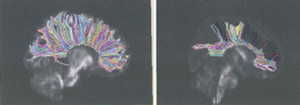

Below is an example of a portion of a DTI study that reflects a normative image of the corpus callosum on the left and the damaged corpus callosum on the right.

Diffusion Tensor Imaging (DTI) – measures the tendency for water to diffuse away from one location in the brain to another. Diffusion is constrained by numerous features of the local cellular environment in the brain, and it is therefore regarded as a measure of local tissue organization. One of the most frequently used DTI measures of tissue organization is termed “Fractional Anisotropy,” or FA. DTI analysis is performed by calculating the FA values for the patient and then comparing FA values at each point across the patient’s brain with FA values across the brains of healthy people.

White matter tracts (as distinct from the gray matter) can be analogized to the “wires” connecting the components or regions of the brain. Those fibers are known as “white matter” because they are covered by white myelin sheaths and are made up of different cellular than the gray matter. White matter fiber tracts are particularly susceptible to damage as a result of the trauma, and that damage can occur as a result of the partial or complete severing of the tract (“axotomy”) or can be damaged as a result of the stretching, twisting or compression of the fiber. The most common areas in the brain’s white matter to be impacted by trauma involved the gray/white matter junction. This area is particularly susceptible to injury because of the relative strength of the different tissue involved. The same biomechanical forces that are applied to the gray and white matter will more likely impact the white matter compared to the more resistant gray matter. The most useful tool for quantifying the structural integrity of white matter fiber tracts is the MRI computer sequence known as Diffusion Tensor Imaging (“DTI”). DTI measures the tendency for water to diffuse away from one location in the brain to another. Diffusion is constrained by numerous features of the local cellular environment in the brain, and it is therefore regarded as a measure of local tissue organization. One of the most frequently used DTI measures of tissue organization is termed Fractional Anisotropy, or FA. To assess the integrity of the fiber tracts, the fibers in a patient with an acquired brain injury are assessed by computing the FA values as previously described, and then the FA values at each point across the patient’s brain are compared with FA values across the brains of healthy people comprising a normative sample.